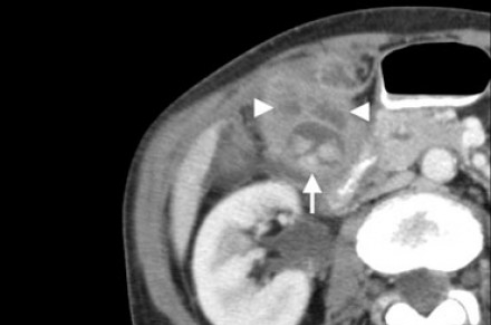

Острый калькулезный холецистит. После контрастного усиления визуализируется растянутый желчный пузырь (белые наконечники) со слегка утолщенной стенкой. Визуализируется камень в шейки желчного пузыря (белая стрелка).

Сверху изображения пациента 62 лет с калькулезным холециститом. На УЗИ визуализируется стенки желчного пузыря растянутые, с субсерозным отеком (указано белыми стрелками) и в просвете желчного пузыря камень и взвесь. На КТ визуализируется переход воспалительного процесса с желчного пузыря на соседние ткани (перихолецистит).